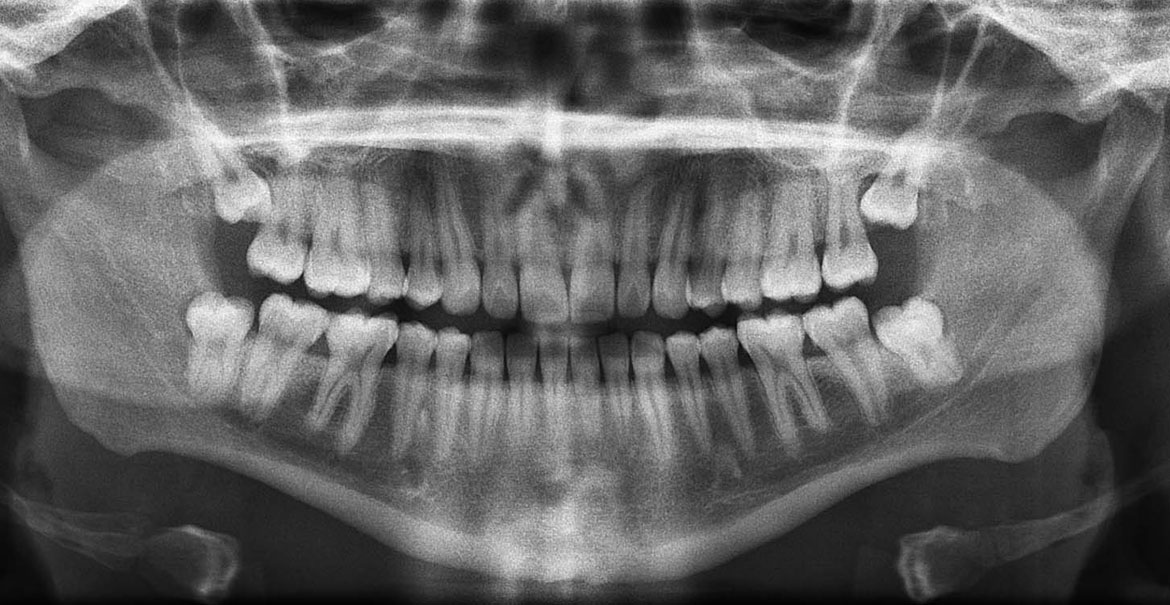

YİRMİ YAŞ DİŞ ÇEKİMİ

20 Yaş dişleri genelde ağız içine çıkmakta zorlanırlar , ya tamamen gömülü kalırlar ya da üzerlerinde bir miktar diş eti parçasıyla örtülü olarak yarı gömülüdürler , nadiren de tamamen ağız içine çıkabilirler.

Tamamen gömülü kaldıklarında etraflarında kistleşme , iltihaplanma gibi riskler içerirler , yarı gömülü olduklarında da iltihaplanma , önündeki dişe zarar verip çürütme , koku nedeni olma gibi sorunlar yaratırlar.

Bu nedenle çoğu zaman çekim uygulanıp ağızdan uzaklaştırılırlar , bu da gömülü ve yarı gömülü olanlarda cerrahi işlemler gerektirebilir.